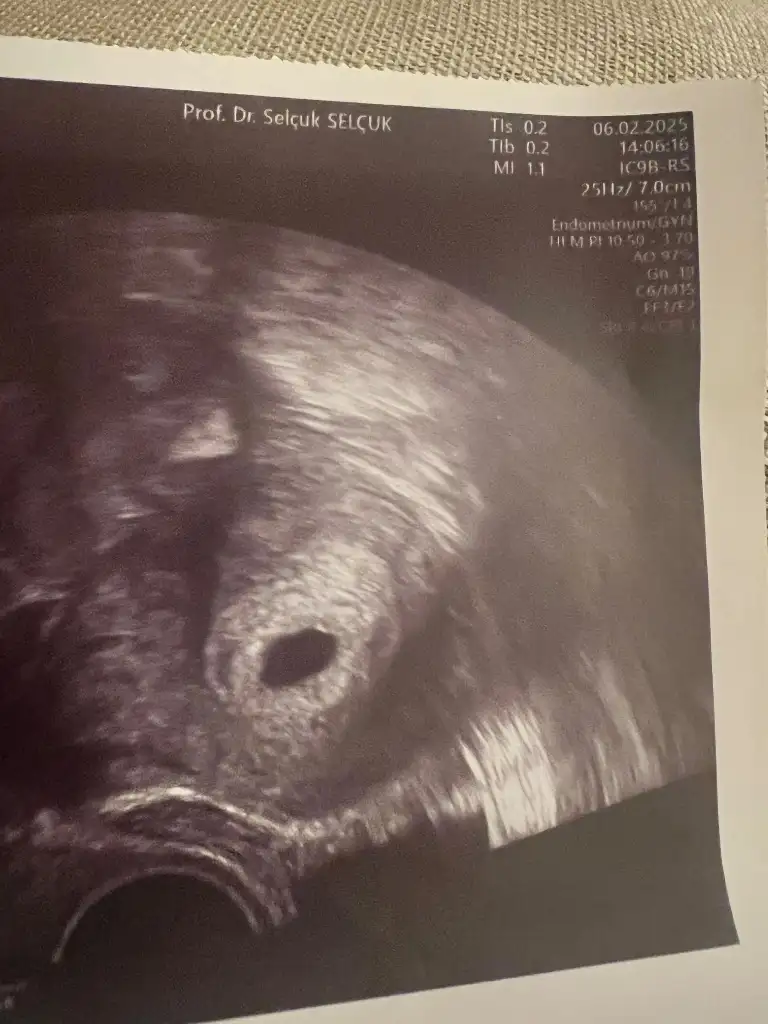

Ölçü söylemedi ama fotoyu ekleyeyim, anlayabilir misiniz acaba?

Eklentiler

• IMG_0470.webp

IMG_0470.webp

37,9 KB · Görüntüleme: 56

Tebrik ediyorum sağlıkla ilerlesin inşallah. Baktım usg fotosuna ama kese ölçüsü yazılmamış. Benden günü önce bir arkadaşın 7 mm çıkmış yukarılarda gördüm. İki olduğu için küçüktür diyip bu vesveseyi sonlandırayım 😁 ne levellar atlattık değil mi burası en güzeli🥰